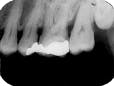

The bisecting-angle technique creates specific errors in vertical angulation, giving shortened images (see Radiograph 2 as an example of foreshortening) or lengthened images (see Radiograph 3 as an example of elongation). Substantially shortened images occur because there is too much vertical angulation. This causes distortion in the reproduction of the actual size of the tooth. The solution requires a decrease of the vertical angulation by at least 10 degrees.

Conversely, lengthened im-ages occur because there is not enough vertical angulation. Another reason is that the film is curved in the mouth. Increasing the vertical angulation by at least 10 degrees and repositioning the film to prevent bending will alleviate this distorted image.